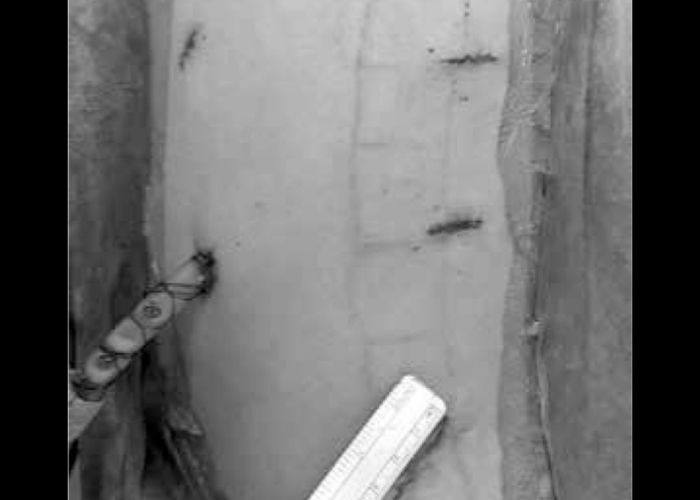

Multidisipliner Skolyoz Cerrahisinde VERTEBRAL Gövde Cerrahilerinin toraks bölümü Videotorakoskopik olarak tarafımca gerçekleştirilmektedir.